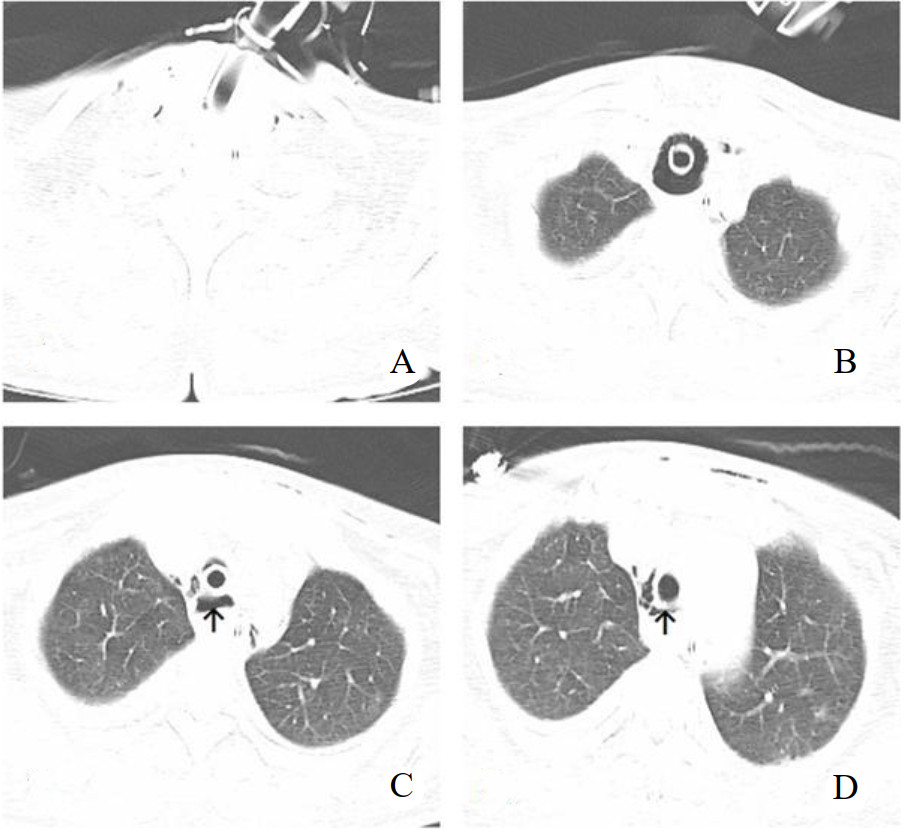

采用Griggs[1]操作技术,器械(型号PW16-S-80-C)由上海全安医疗器械有限公司提供。Seldinger穿刺成功后放入导丝,专用扩张钳扩张皮下组织和气管前壁,置入气管切开套管。放置套管后拔除导丝,导丝出现弯曲,气管切开套管未见气体溢出,考虑气管切开套管异位,再次尝试2次,未能成功置入气管切开套管。后经纤维支气管镜通过气管插管口入镜实时观察,先经切口处放入导丝,在导丝引导下置入气管切开套管,纤维支气管镜证实气管切开套管在位并吸除气道内痰液和血液。术后第2天复查胸部CT提示:纵隔和颈部少许积气,气管切开套管开口层面正后方可见气腔(图 1)。第3天患者出现肺顺应性下降,潮气量降低,吸痰管难以进入,气道内吸出少量血性痰。考虑出现紧急气道情况,立即行床边纤维支气管镜检查,经气管切开套管入镜,见软骨环,膜部有血凝块,经过气管切开套管下约1~2 cm后纤维支气管无法伸入远端,考虑血凝块伴多发纤维素样组织形成,血凝块无法吸出,试用活检钳捣碎血凝块亦未能吸出。患者肺顺应性差,高参数机械通气[压力控制通气(PCV)模式,吸入氧体积分数100%,PEEP 12 cmH2O(1 cmH2O=0.098 kPa),高于PEEP压力控制20 cmH2O,吸呼比1∶2,呼吸频率14次/min] 经皮氧饱和度约94%。当时因为极度担心血块完全阻塞气道,所以在负压状态拔除气管切开套管重新置入后通气明显改善,纤维支气管镜证实气管切开套管在位,未见血凝块。为明确原因,笔者予可视喉镜联合纤维支气管镜引导下经鼻气管插管成功,同时拔除气管切开套管,在纤维支气管镜(经鼻气管插管入镜)监视下逐渐地外拔气管插管,可见气道约6点钟方向气管膜部假腔形成,撕裂起始部位约在气管切开套管管口附近。后再次经鼻入镜,经过声门后气管插管气囊放气,经气管插管旁路入镜观察膜部假腔情况。笔者推测患者气管切开套管角度改变(往正后方方向),此时大部分气管切开管口对准假腔,护士吸痰管进入假腔,反复多次吸痰导致组织损伤伴出血,血凝块形成,负压状态下拔出气管切开套管时把血凝块带出,再次置入时幸运地置入气管真腔。为建立确切有效的人工气道,考虑重新留置气管切开套管有再次置入假腔可能,且常规气管切开套管难以通过真假腔分隔处,予逐渐外拔气管插管尖端水平位至气切口上方,在纤维支气管镜引导下经皮肤切口置入加长型气管切开套管,经纤维支气管镜证实气管切开套管尖端通过假腔分隔处,患者肺顺应性明显改善,吸痰管吸痰通畅。纤维支气管镜检查见图 2

A:颈部少许皮下气肿;B:气管切开套管气囊部位未见明显异常;C:气管切开套管开口层面可见少许纵隔气肿,正后方可见气腔;D:气切套管下约1 cm层面,见气腔缩小;箭头示气腔 图 1 患者经皮扩张气管切开术后胸部CT